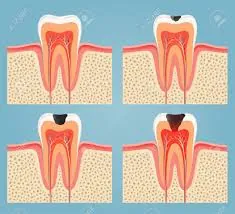

• RESTAURACIONES SIMPLES Y COMPLEJAS (EMPASTES)

• ENDODONCIAS (DESVITALIZACIONES)